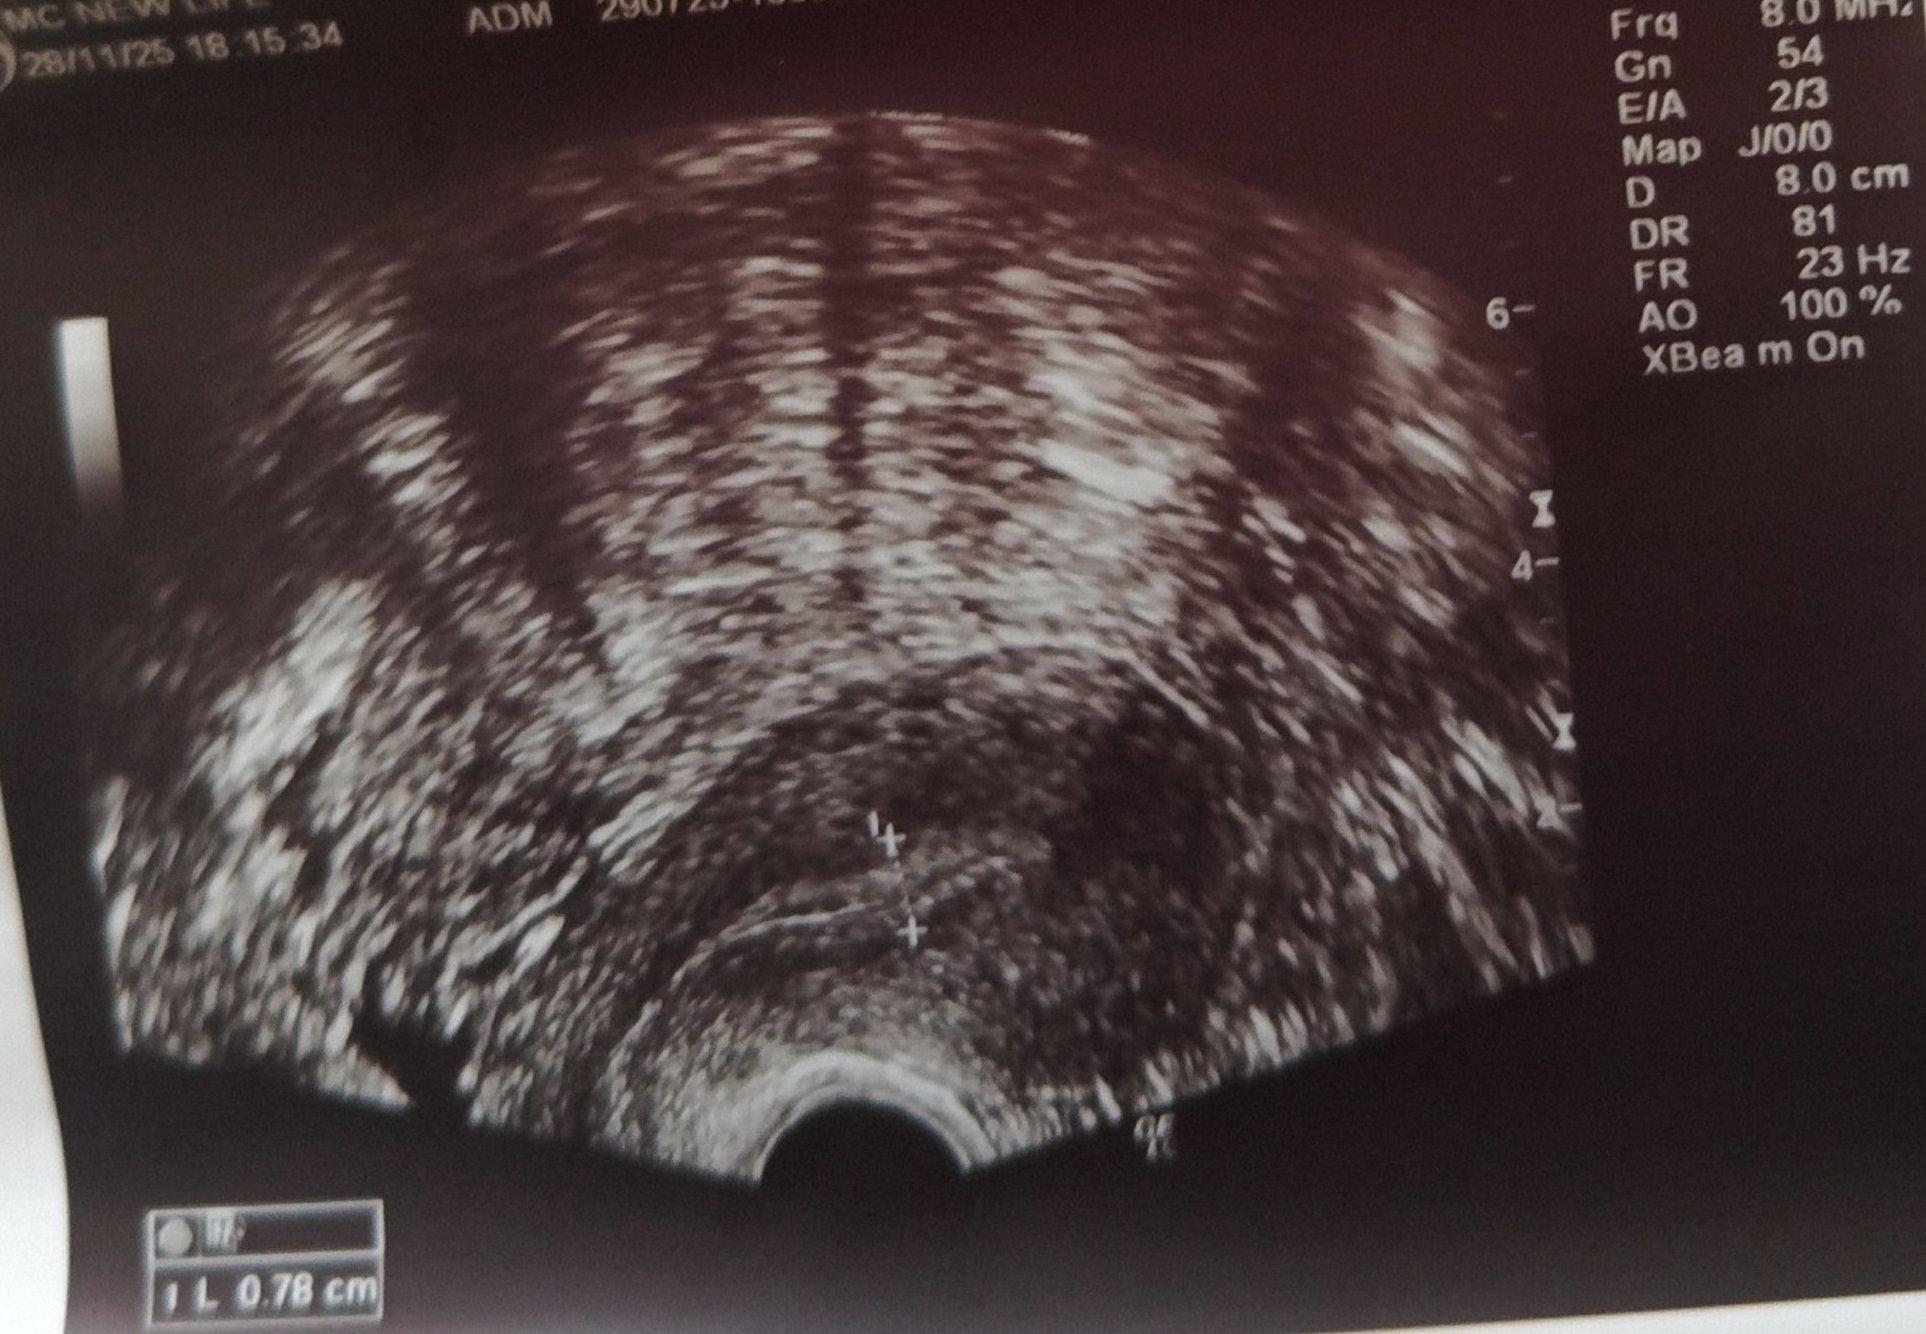

Какво представлява изображението от ехографията на 5-седмична и 2-дневна бременност?

Какво представляват белите точки в плодния сак на ехографската снимка?